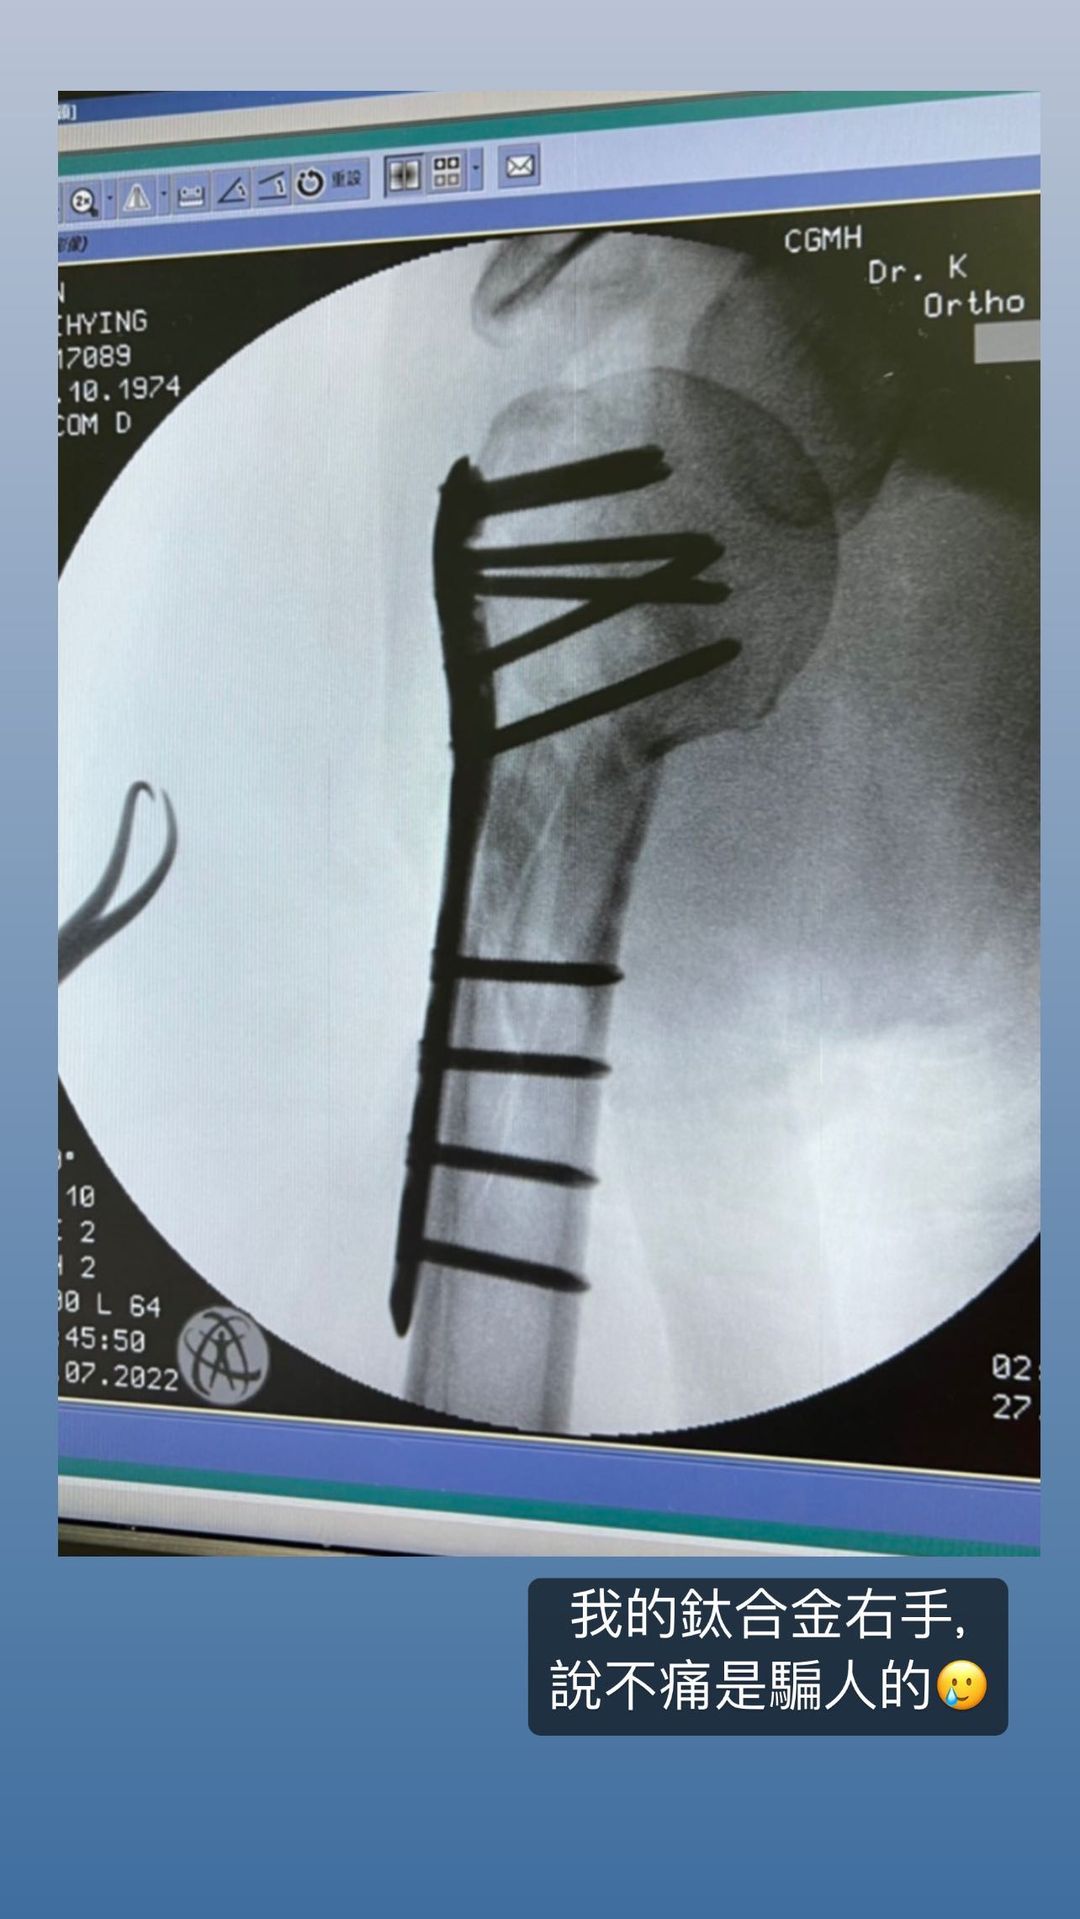

林志颖贴出X光片表示“钛合金手臂需要时间训练”,X光片中可见他的骨头中被植入钛合金固定,当初伤势严重程度可想而知。

林志颖贴出X光片表示“钛合金手臂需要时间训练”,X光片中可见他的骨头中被植入钛合金固定,当初伤势严重程度可想而知。